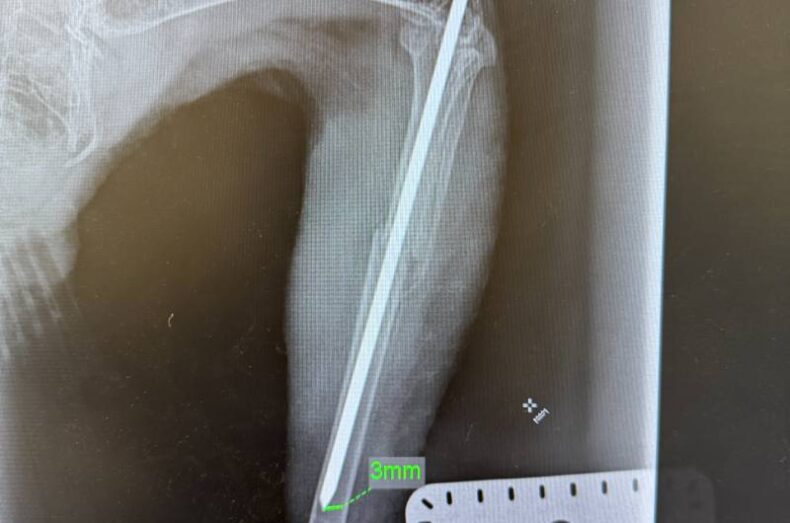

After being put out in the flight aviary, as usual, later in the day that Stanway could not bear weight on his left leg. The team did not know what he had done but took him to see the Vet. The Vet could feel a break in the leg, so Stanway stayed at the vets for X Rays and further checks with the Orthopaedic Surgeon, to see if his leg was fixable.

It was a clean, mid-way break so his leg could be fixed, but meant a brief time being contained in the cage to stop him moving about too much and causing more damage, until he could be operated on. (Broken leg x-ray second and third image below).

The Veterinary Centre’s Orthopaedic Surgeon explained Stanway’s leg would be pinned both sides of the break, after a rod had been inserted into the leg bone, and then an external fixator would be fitted to ensure everything stayed where it should whilst healing took place. The centres Veterinary Nurse very kindly shared photos and x-rays of the procedure.

Three weeks after the first check, Stanway needed a couple more of XRays to make sure the bones were knitting together. The brilliant news was all was working, and the bones were starting to callous over. Stanway did not seem impressed with the prospect of another two weeks of cage rest, and we can’t blame him, it must have been very confusing for this wild buzzard.

After another three weeks of cage rest, a check showed all was going well, so under anaesthetic, the Orthopaedic Surgeon, from the Veterinary Centre proceeded to remove the rod and fixator. (Post operation image and later x-ray after rod removal images below)